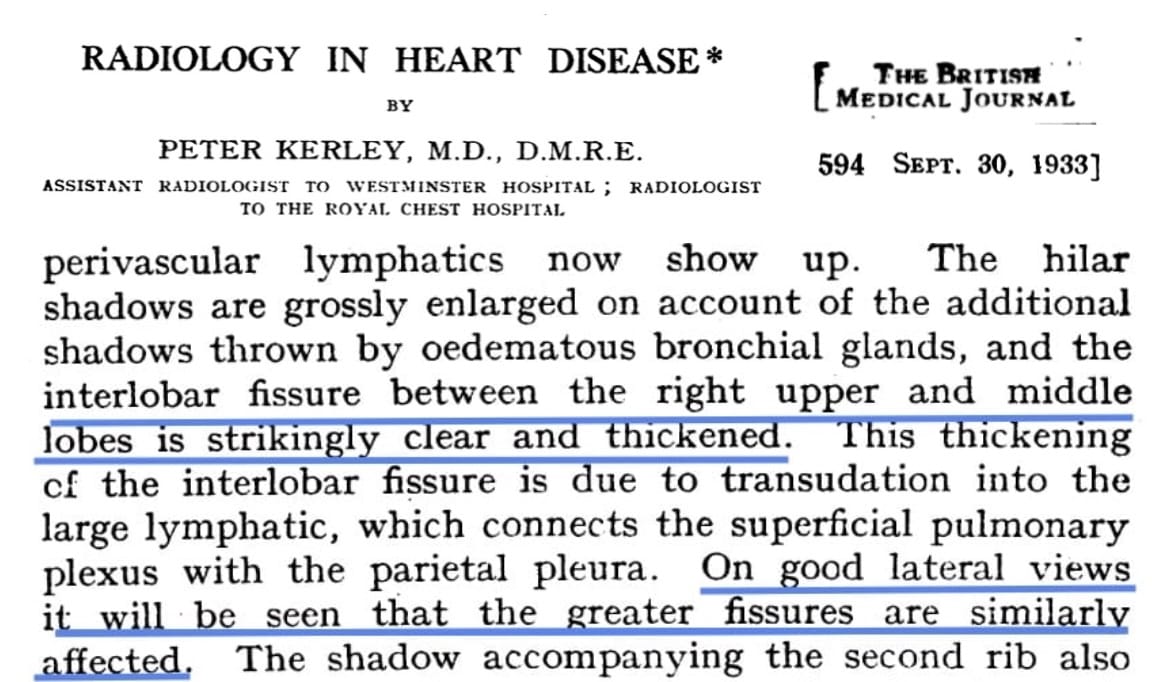

- apparent thickening of the interlobar fissures

When two of these sub-visceral pleural compartments are contiguous, as is the case in relation to the interlobar fissures, the accumulating fluid (blue asterisks) suggests “thickening” of the fissures.

Traditionally, the horizontally-oriented, short lines above the lateral costophrenic sulci on frontal radiography are termed Kerley B lines; those in proximity to the hila, Kerley A lines; and those imaged en face, perceptually a reticular-type network, Kerley C lines.